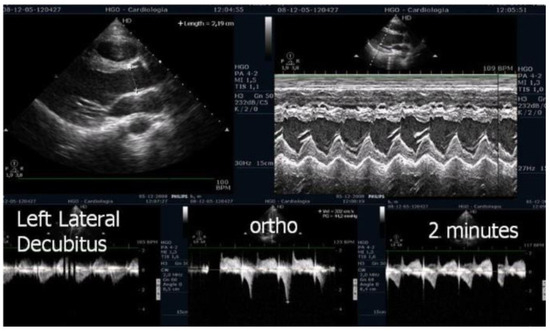

ESE’s potential extends beyond diagnosis, as it may guide targeted therapy. Our experience supports its value in initiating β-blockers in selected pediatric cases (Figure 1 and Figure 2) [1,9].

Figure 1.

This figure shows an intraventricular gradient during exercise in an adolescent experiencing exercise-related chest pain and syncope, accompanied by elevated troponin levels (top). A significant reduction in the gradient is observed under beta-blocker therapy (bottom).

On the resting echocardiogram, all the exams were considered normal with and without beta-blockers. No wall motion abnormalities were detected in any of the exams, with or without beta-blockers. In the complete group, IVPG (Figure 1) at peak exercise on the first assessment was 105 ± 38 mmHg, with mitral valve SAM in 28 adolescents (Figure 2). Among the 29 adolescents treated with beta-blockers, IVPG was 58 ± 32 mmHg, p < 0.0001.

In our study, beta-blocker therapy was associated with reductions in heart rate, exercise-induced ST-segment alterations, systolic blood pressure, and, consequently, peak heart rate–systolic blood pressure product (HR × SBP). The incidence of intraventricular gradients (IVGs) (Figure 1) and systolic anterior motion (SAM) of the mitral valve (Figure 2) during exertion also decreased significantly. These hemodynamic improvements were accompanied by a notable reduction in symptoms during exercise testing and follow-up